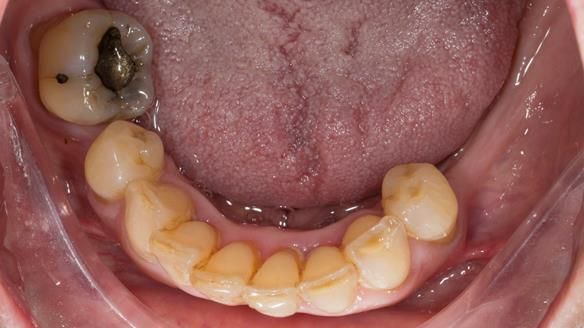

In this edition, I present the removable partial denture treatment for Jean, an 80-year-old woman with a sore mouth caused by a soft tissue-supported 'gum stripper' acrylic denture and a clenching habit. Below, I outline the step-by-step process of her treatment. It wasn't straightforward; I had to remake the denture after it fractured to achieve a satisfactory result. Each patient is unique, and sometimes a new RPD serves as a prototype. Occasionally, I need to make adjustments, learn from any mistakes, and refine the design to get it right.